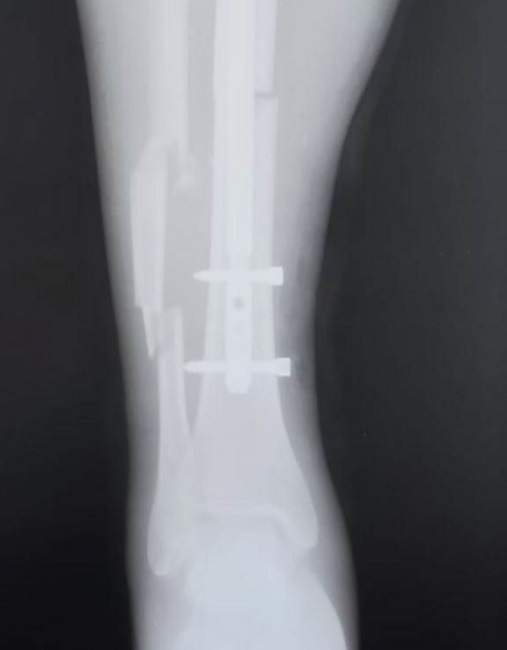

Пациентка поступила в ООКБ в тяжёлом состоянии. Медики диагностировали множественную травму (включая «открытый многооскольчатый билокальный перелом левой бедренной кости со смещением»).

Вначале мотоциклистка находилась в реанимации. Врачи областной больницы сделали остеосинтез. Так называется хирургическая операция, при которой костные отломки соединяют и фиксируют с помощью металлических конструкций. Работа шла около четырёх с половиной часов.

«В данном случае представляет интерес раннее полное оперативное лечение сложных открытых переломов, выполненное по всем правилам современной травматологии», – отметили в соцсетях ООКБ.